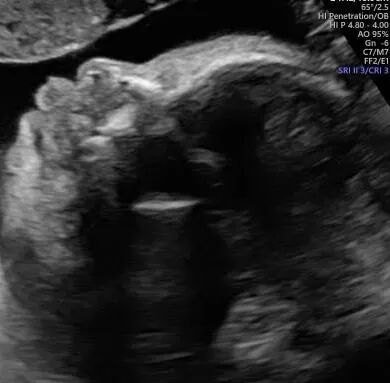

在怀孕八周时,胚胎进入了关键的发展阶段,体长约1.6厘米,已经开始显示复杂的生理特征和明显的人类形态。这个时期,胚胎的大脑结构如脑室和脑裂开始形成,基础心脏也已经开始跳动,并将分为两个房室,已经可以听到宝宝强壮有力的心跳声了。恭喜我们的准爸爸,我们都非常期待在接下来的检查中看到宝宝更多的成长和发展情况。